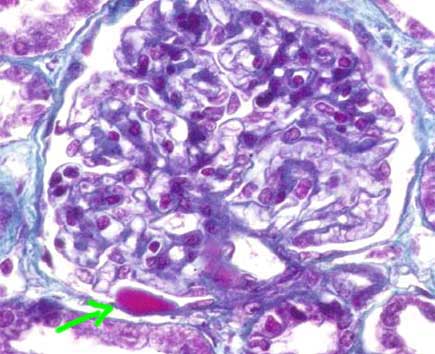

Otras dos lesiones glomerulares, llamadas exudativas (al igual que la hialinosis arteriolar), son la gota capsular y la hialinosis glomerular. La primera es un depósito homogéneo, hialino, en la cápsula de Bowman, suele ser redondeado o elongado y es altamente sugerente de ND, aunque no patognomónico (puede verse muy ocasionalmente en hipertensión y otras lesiones glomerulares nodulares idiopáticas). La hialinosis glomerular resulta de la extravasación de componentes plasmáticos que se acumulan en segmentos periféricos del penacho capilar, es también llamada gorro hialino o gorro de fibrina ("hyalin cap" o "fibrin cap") (Figuras 6, 7 y 8). En muchos casos con lesions típicas se evidencian microaneurismas producidos por mesangiolisis (Figuras 8 y 9).

Figura 7. En este glomérulo hay leve incremento de la matriz mesangial. La flecha señala una hermosa gota capsular, otra de las lesiones exudativas de la ND; lesión "casi" patognomónica de esta glomerulopatía (ver texto. En esta imágen la vemos fuschinofílica (roja), pero en otros casos puede verse de un tono verde o azul; compare con las gotas capsulares de la Figura 8. (Tricrómico de Masson, X400).

Figura 8. En esta imagen podemos ver cuatro alteraciones de la ND: ensanchamiento mesangial por expansión de la matriz; hialinosis arteriolar, en este caso nodular (flechas azules); dos gotas capsulares, una en cada glomérulo (flechas rojas, delgadas); y microaneurismas (flechas verdes), lesiones frecuentes en ND que se suelen asociar a áreas focales de mesangiolisis. (Tricrómico de Masson, X400).